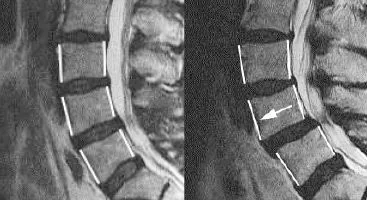

Post-Operative Degeneration and Slippage of Spine (Spondylolisthesis)

Sally had surgery on her lower back in 2006 (L4-5 laminectomy). She had recurrent incidental back pain post-surgery, but in 2012 her back pain...